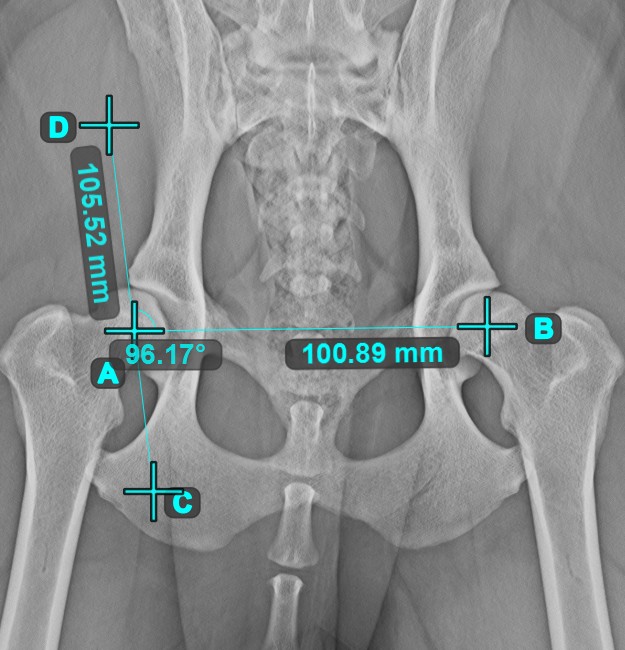

Angle from 3 Points¶

The Angle from 3 Points tool is a simple and effective way to calculate an angle from just three points.

Start by selecting the tool from the left toolbar and assign it to one of the available mouse buttons. Place the start point of the initial side, the vertex, and the end point of the terminal side of the angle, or select the points from the scene. The sides of the angle will be automatically constructed, thus calculating the angle between the lines.

Modify the position of the three points to change the arc of the angle by using the Select/Move Item tool.